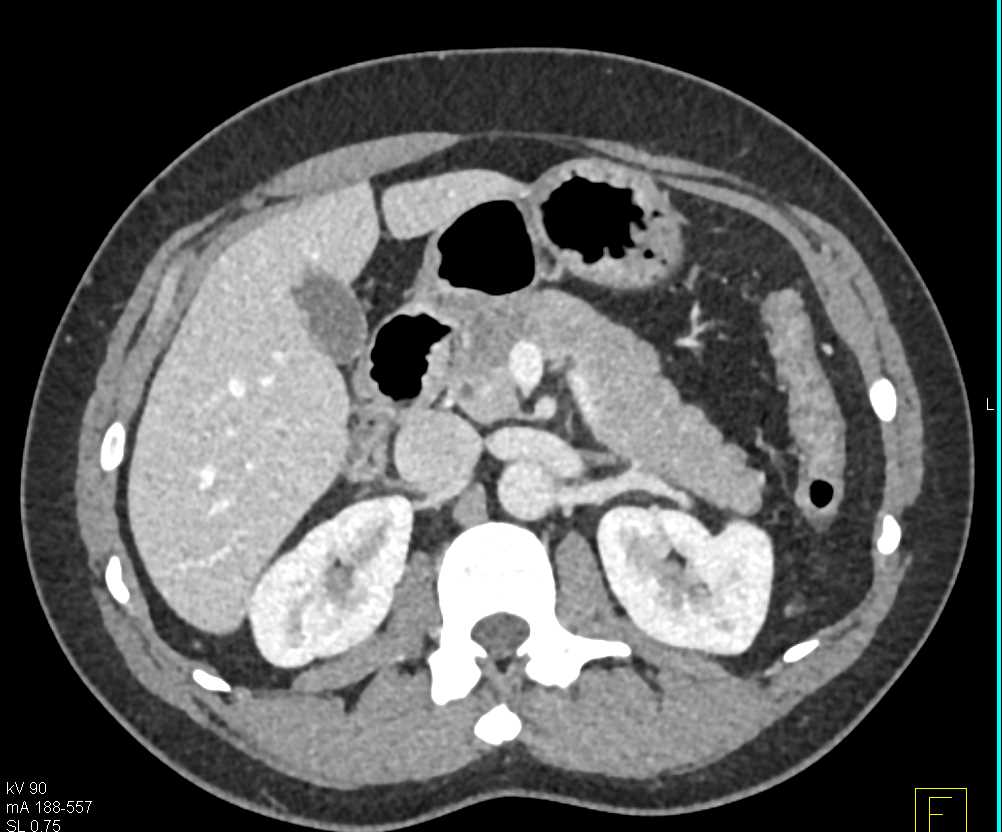

Carcinoma Head of Pancreas